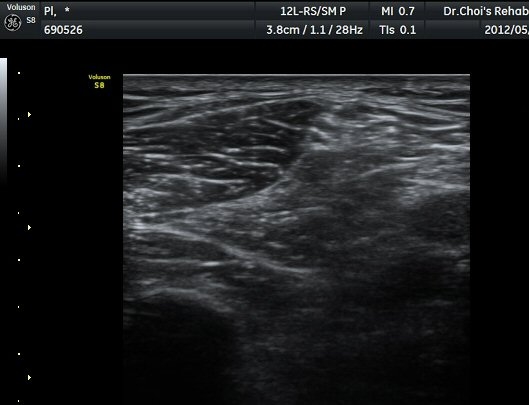

ŽÃËÀÚ¸¦ ¾Æ·¡·Î À̵¿ÇÏ¿© ºñ°ñµÎ ºÎÀ§±îÁö ÃѺñ°ñ½Å°æÀÇ ÁÖÇàÀ» µû¶ó ½Å°æÀ» È®ÀÎÇÏ¿´´Ù(±×¸² 3, 4).